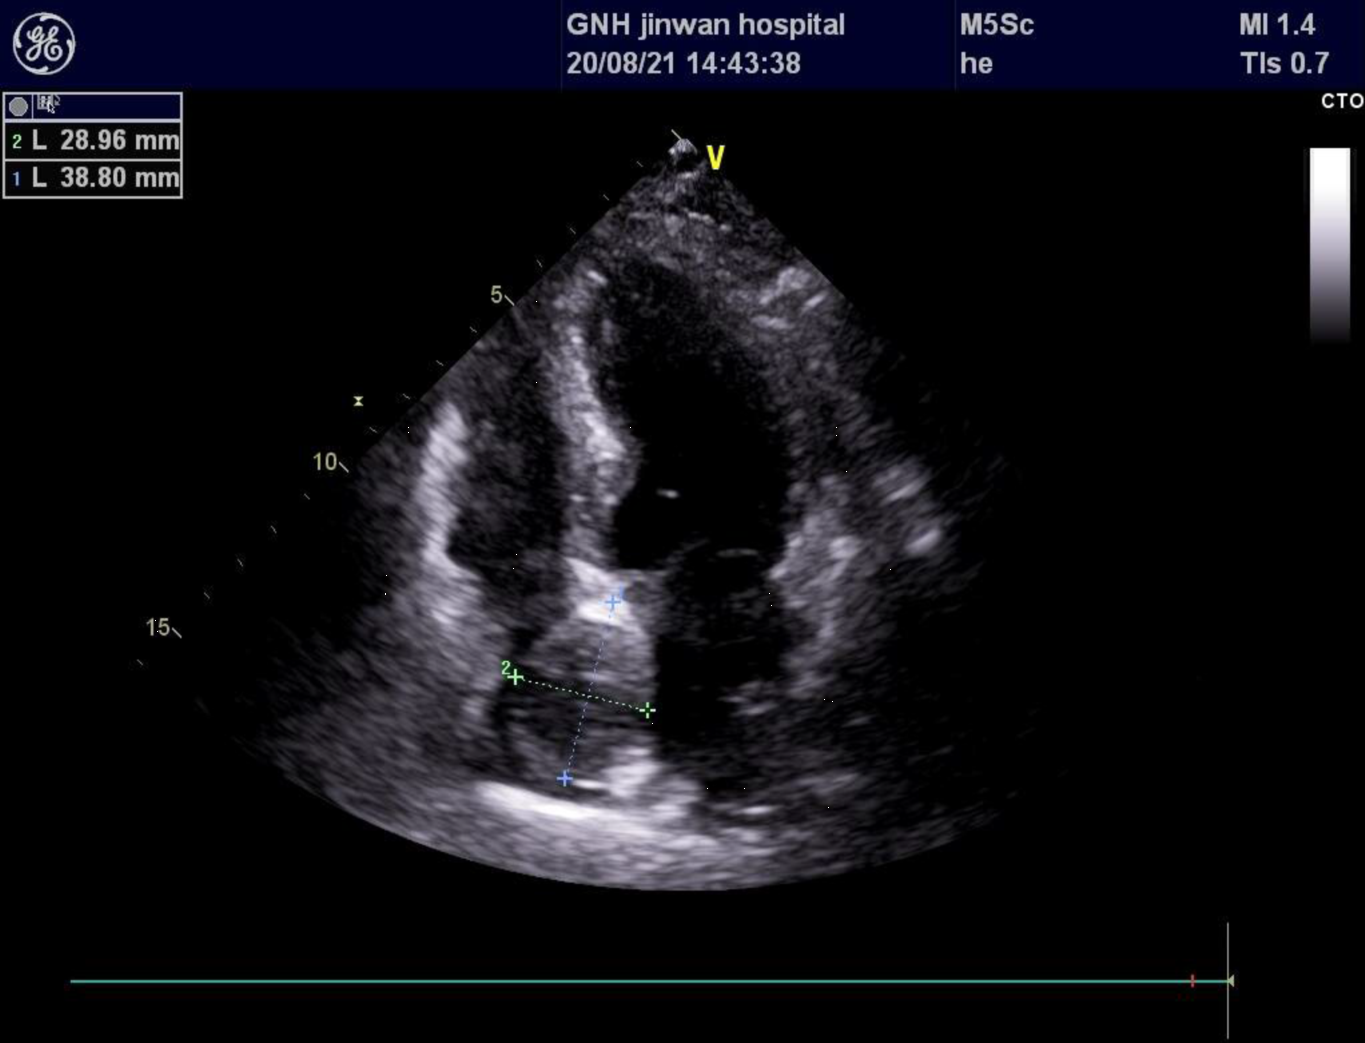

經過詳細的問診和查體後,省醫珠海醫院心血管科郭曉碧主任意識到李伯伯的心率加快可能不簡單,於是開出了心臟超聲檢查。由廣東省人民醫院委派、常駐省醫珠海醫院的心臟超聲專家何亞樂主任經仔細檢查發現,在李伯伯心臟房間隔的右心房面有一團若隱若現的腫塊,性質不明。為了進一步明確腫塊的性質,在一個晚上的禁食準備後,何亞樂主任第二天早上為李伯伯進行了經食道心臟超聲檢查。

根據患者房間隔腫塊的超聲表現,憑藉多年的檢查經驗,何亞樂主任很快就辨認出了這是一例罕見的房間隔脂肪瘤,腫瘤大小已達4×2cm,如果不儘快切除,隨着腫瘤繼續侵犯房間隔組織有可能會造成傳導阻滯、更為嚴重的心律失常,甚至心功能不全等危險!

術前心臟彩超檢查發現房間隔右房面佔位性病變